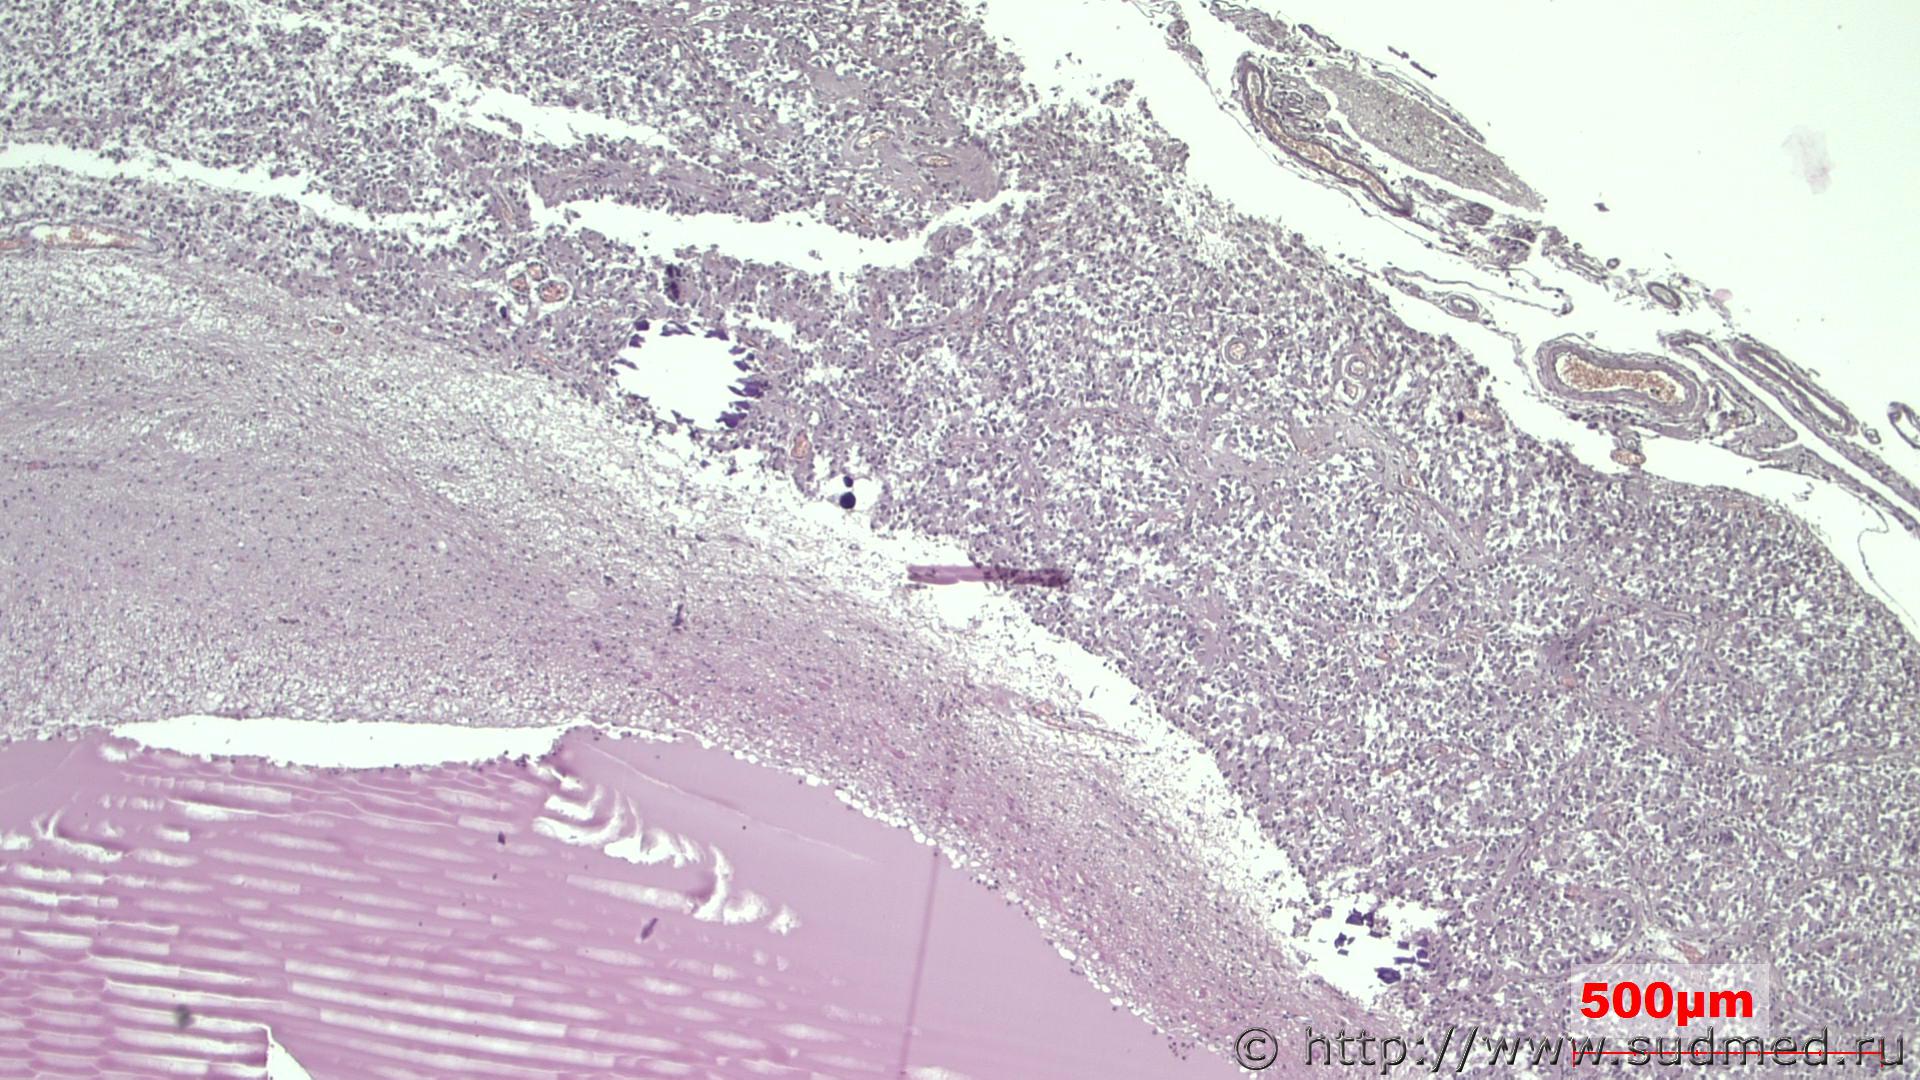

Вот она.

Похожа ?

Аналогичное альвеолярное строение.

В вашем фото есть уродлиыве ядра, а у ТС нет. Альвеолярный рисунок сосудистой стенкой. Эпителиальная субэпендимома с кальцификацией и псевдокист в г/м, учитывая вблизи желудочков и сосудистого сплетения.